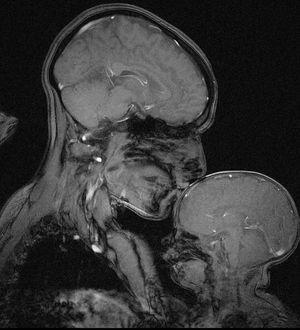

MRI of a mother tenderly kissing her 2-month-old child.Indeed, MRI detects changes in our bodies that can save our lives, but it also captures pure love.